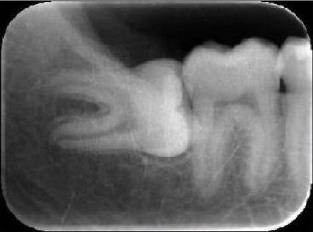

2、小牙片:就是隻能看到一兩(liang) 顆牙齒牙根情況的那種牙片,一般主要用於(yu) 查看牙根管、牙根等情況。價(jia) 格一般在幾十上百元左右,是牙片中比較便宜的一種。如下圖:

根管治療拍片